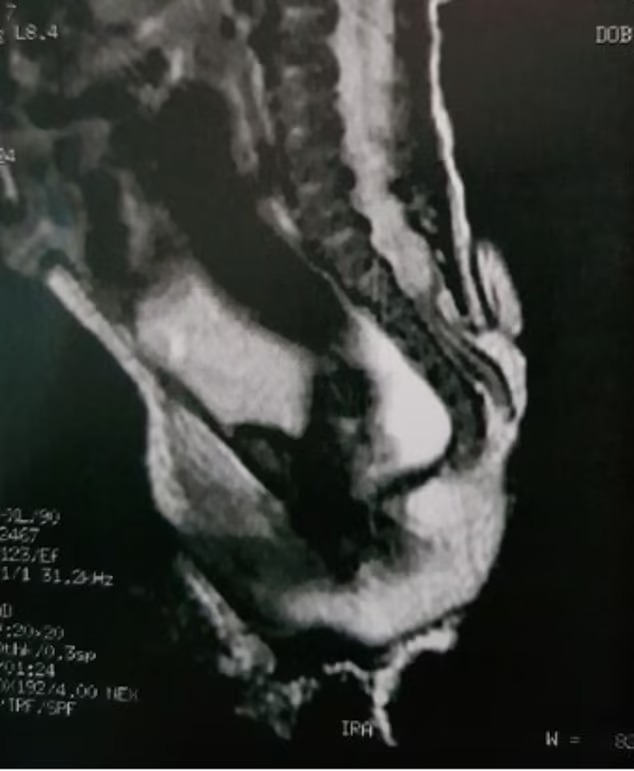

وولدت الطفلة بعيب يُدعى السنسنة المشقوقة، وهو ظاهرة نادرة تحدث في العمود الفقري حينما يكون الطفل لا يزال في الرحم، وهو ما يسبب فجوة وتغيرات في العمود الفقري.

وقال الأطباء إن الذيل انتشر من المنطقة القطنية العجزية، وهي المنطقة التي تربط العمود الفقري بالحوض، كما شخّصوا الزائدة على أنها ذيل بشري زائف، وهو نمو يشبه الذيل ولكنه ناتج عن مشاكل العمود الفقري أو الأورام.